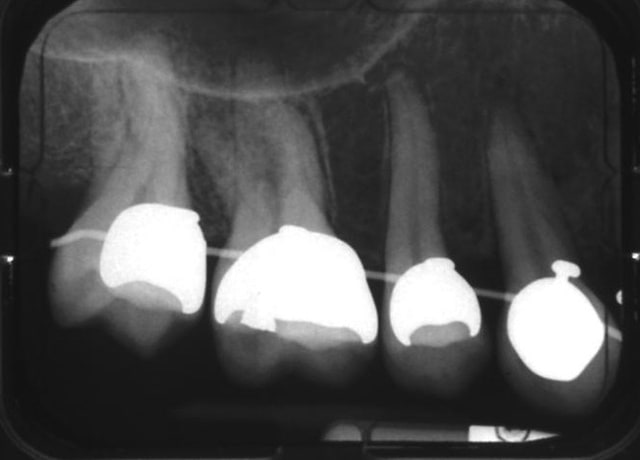

bon les gars, si on part du principe qu'il faut que je m'inquiète pour ces dents-là, alors il faut que j'en fasse autant pour ces 16 et 26, avec leurs épaississements ligamentaires...

et on est pas sorti de l'auberge...

16 dd4xmj - Eugenol

26 djjirf - Eugenol

>

Toujours une carie sous amalgame...

;-(

> Toujours une carie sous amalgame...

> ;-(